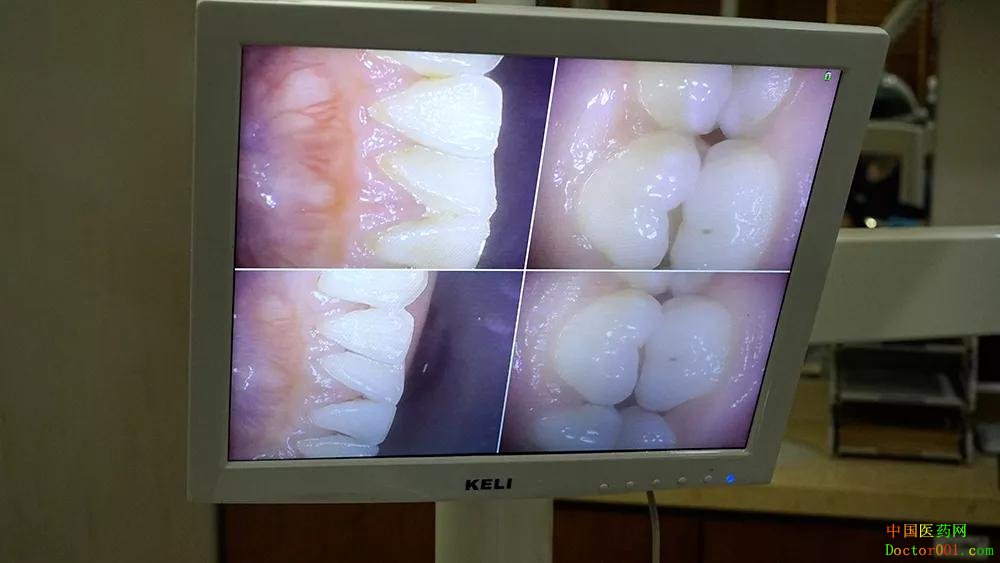

偶尔洗到比较敏感的牙齿 只要举手,医生和护士姐姐就会停下来 问我需不需要休息一下 弄得我都有点不好意思了 大约过了半小时后洁牙完毕 再次把洁牙后的牙齿状况投放在屏幕上 牙龈上的结石都被洗干净了 牙齿看起来干净、光滑了好多 连呼吸都轻松了很多